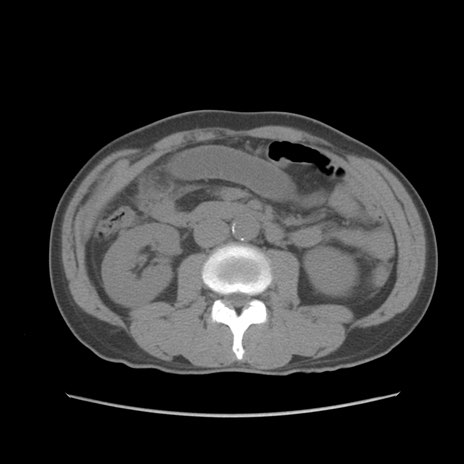

症例56 CT(横断像)

脂肪ウインドウ